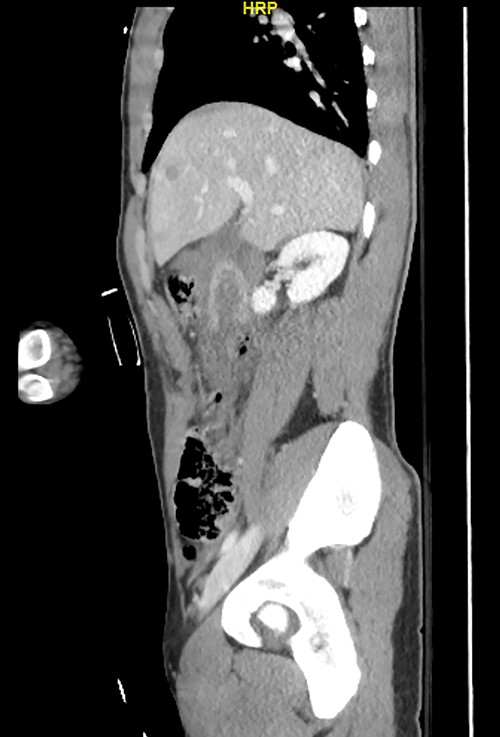

Here, we report a case of a 21-year-old man who was admitted to our hospital following a motor vehicle collision where he was a pedestrian, hit by a car and pushed against the bumper of another car. Upon arrival to the hospital, he was conscious and oriented, with normal vital signs. Abdominal examination revealed ecchymosis over the epigastric area with tenderness, however, no distention was noticed. Focused assessment with sonography for trauma result was positive in the right upper quadrant. His initial blood test results revealed a white blood cell (WBC) count of 26.5 × 109 cells/l and a hemoglobin level of 150 g/l. His serum amylase and lactic acid levels were 92 U/l and 4.53 mmol/l, respectively. His base deficit was 4.3. He underwent abdominal computed tomography (CT) with oral contrast, which showed query duodenal and possible pancreatic transection with active arterial extravasation (Figs 1–3). In addition, CT revealed a comminuted right intertrochanteric femoral fracture without associated vascular injury.

Exploratory laparotomy was performed, which revealed ~500 ml of blood in the peritoneal cavity, central retroperitoneal hematoma, peripancreatic hematoma and complete transection of the third part of the duodenum. The retroperitoneal hematoma and peripancreatic hematoma were nonexpanding. A formal end-to-end anastomosis of the third part of the duodenum was performed using 3–0 polydioxanone (PDS) in a single layer. Double decompression of the duodenum was achieved using a nasoduodenal tube (ND) and a retrograde duodenostomy tube. A jejunostomy tube was created for feeding as well.

Despite its limitations in distinguishing between duodenal hematoma and duodenal perforation, CT with intravenous and intraluminal contrast remains the gold standard diagnostic test in stable patients with blunt abdominal trauma [1]. In the reported case, CT revealed duodenal and possible pancreatic transection with active arterial extravasation.